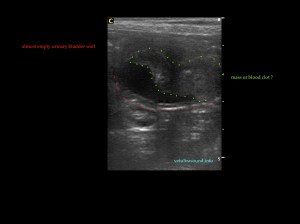

Τα πήγματα αίματος πολλές φορές μπορεί να προσομοιάζουν μάζες της ουροδόχου κύστης, ειδικά αν δεν είναι αρκετά γεμάτη ή δεν έχουν σχηματιστεί πρόσφατα. Σε αυτή την περίπτωση περιμένουμε να γεμίσει ώστε να εξετάσουμε:

– αν έχει αιμάτωση η μάζα που εντοπίσαμε

– αν προσφύεται στο βλεννογόνο

– αν μετά από αλλαγή θέσης του ασθενή μετακινείται

Blood clots can resemble masses, especially when the urinary bladder is not fully distended or the clot was not recently formed.

Tips for differentiating a blood clot from a mass (when cytology results are not well defined):

– Evaluation of blood flow in the mass with colour/power Doppler

– The mass should invade the mucosa (if we can see the mucosa enclosing the neck of the mass)

– Changing the patient’s position may reveal that this ‘’mass’’ is not attached to the bladder wall

– Revaluate the patient the next day (the clot may have gone away) or allow the patient to go for a walk and revaluate.